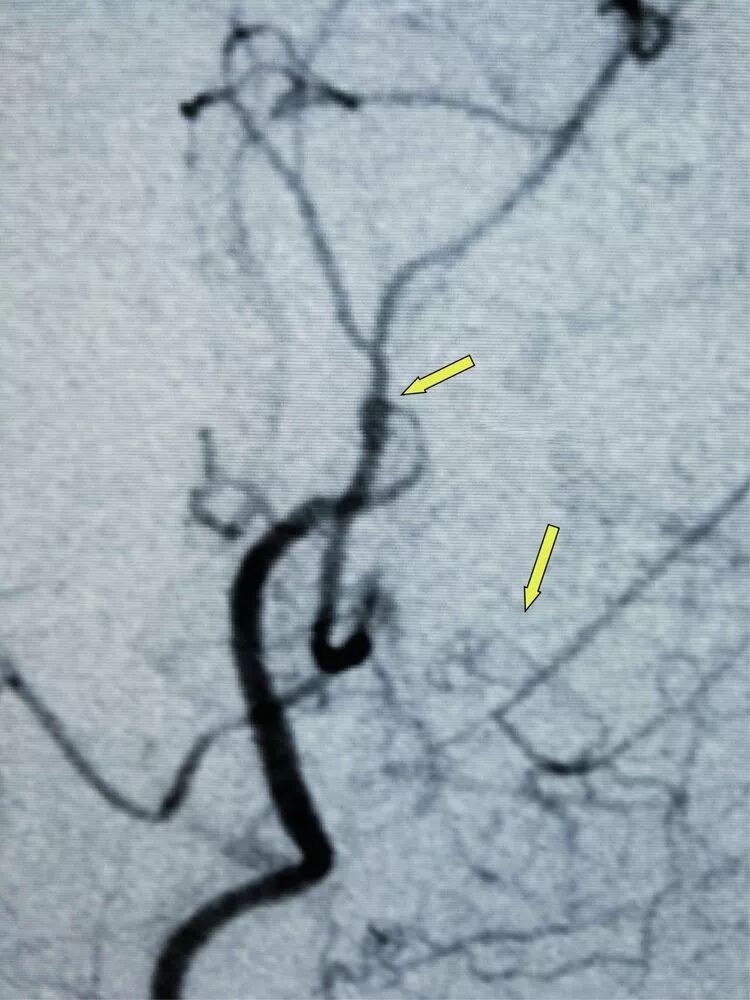

箭头所示为颞浅动脉(供血动脉)与左侧大脑中动脉M4段(受体)经精密的缝合吻合到一起。

患者术后1个个月和3个月分别复查CTA及DSA见血管吻合确切,血流通畅。

术前(左侧)与术后(右侧)左侧大脑半球供血血流的对比,术后患侧大脑半球血运很大程度增多。